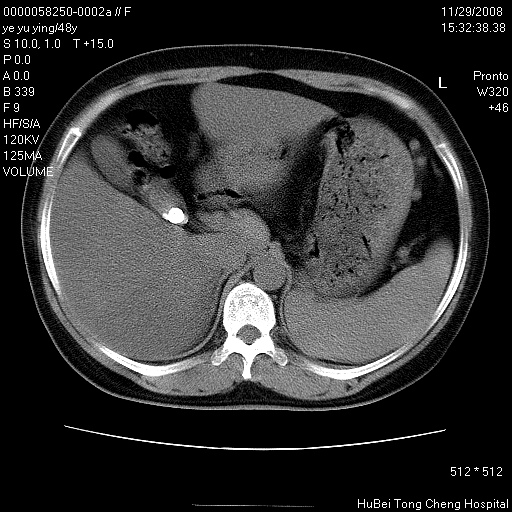

以下是引用zsl6918在2008-11-29 21:47:00的发言:[br]恶性肿瘤病史,转移瘤首先考虑。脂肪肝,胆囊结石。

以下是引用huenhao在2008-11-29 22:11:00的发言:[br]脂肪肝,胆囊结石。左肺病灶建议定期复查。

以下是引用liuyue在2008-11-30 5:44:00的发言:[br]1.左肺病变,首先考虑感染性病变,转移待排;建议治疗后复查。[br]2.肝脏密度普遍减低,考虑与化疗有关。[br]3.胆囊结石.